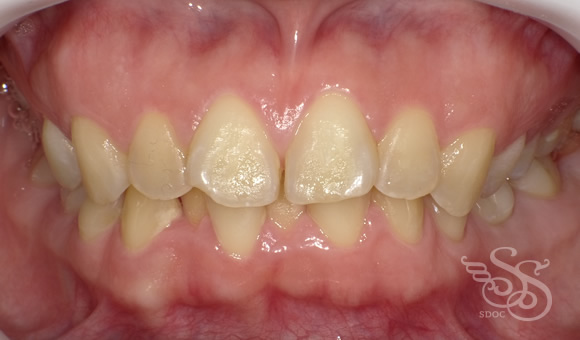

正面:術前

ぱっと見はある程度キレイに並んでいるのですが

前歯がフレアーアウト、前に傾いてしまっています。

こんな感じにフレアーアウトしたフィニッシュになりがちですね。

口もとの突出感も気になります。